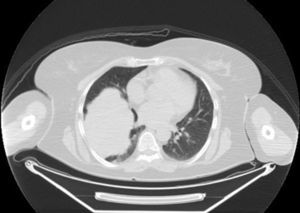

Presentamos el caso de una mujer de 55 años, no fumadora y sin antecedentes de interés, que consultó por dolor torácico tras traumatismo. En un primer momento se realizó una radiografía de tórax con hallazgo incidental de una tumoración pleuropulmonar derecha. La paciente no presentaba clínica respiratoria asociada con pruebas de función respiratoria normales. Se completó el estudio con una tomografía axial computarizada (TAC) de tórax, que mostró una tumoración del tercio inferior del hemitórax derecho en íntima relación con el diafragma y estructuras cardiomediastínicas (fig. 1), y con una punción con aguja fina que mostró tejido compatible con tumor mesenquimal de células fusiformes. Ante estos hallazgos, se optó por intervención quirúrgica, al considerarse el tratamiento estándar, realizando una extirpación completa de la tumoración. La anatomía patológica confirmó la presencia de un tumor fibroso solitario con áreas fusocelulares con elevado índice mitótico, importante pleomorfismo y elevada celularidad (cumpliendo los criterios de malignidad descritos por England et al.), y con positividad inmunohistoquímica para vimentina y CD343. Se desestimó tratamiento adyuvante debido a la baja quimiosensibilidad de esta estirpe tumoral y a los escasos datos al respecto. Se iniciaron revisiones normales hasta que un año después, en una TAC de control se observaron 2 lesiones nodulares muy próximas entre sí (18 y 13mm) con aspecto radiológico de malignidad, por lo que se indicó resección de las mismas. La anatomía patológica confirmó su origen tumoral compatible con metástasis de TFSP. A los 6 meses, un nuevo TAC mostró múltiples nódulos pulmonares bilaterales y afectación ósea confirmada por gammagrafía. Tras ser valorada por el servicio de oncología médica, se solicitó la realización de la mutación de c-kit, al existir casos descritos con dicha mutación y períodos de larga respuesta a imatinib4. Finalmente, se trató de un tumor c-kit negativo, por lo que se decidió iniciar tratamiento con quimioterapia, mostrando rápida progresión a las distintas líneas de tratamiento, falleciendo al poco tiempo del diagnóstico de la recidiva.